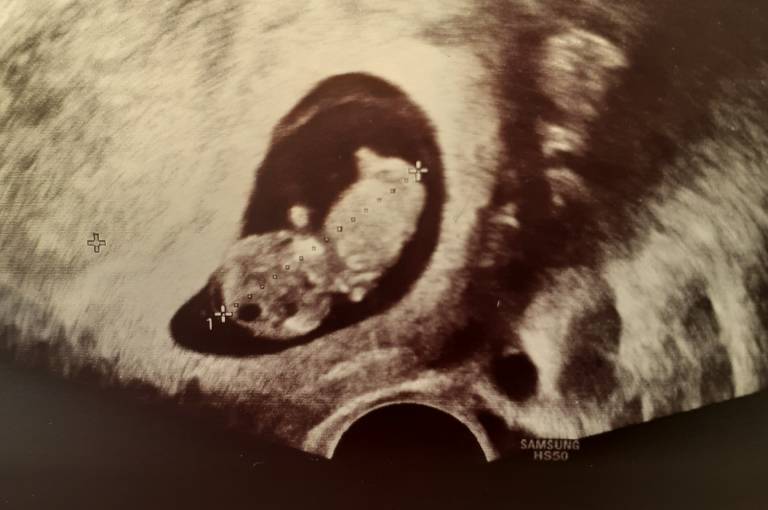

Znalazlam sobie nowy powod do schizy. Choc lekarka zlego slowa nie powiedziala na temat mojej ciazy to martwie sie czy aby Okruszek jest odpowiednio duzy jak na ten tydzien crl 0.67cm 6t4d a pecherzyk zoltkowy 4mm. Znacie sie moze na tym?? Dla mnie to czarna magia a nastrpna wizyta za 2 tyg. Tym razem zrobie liste z pytaniami bo dzis o wszystkich zapomnialam.. z tego szoku..